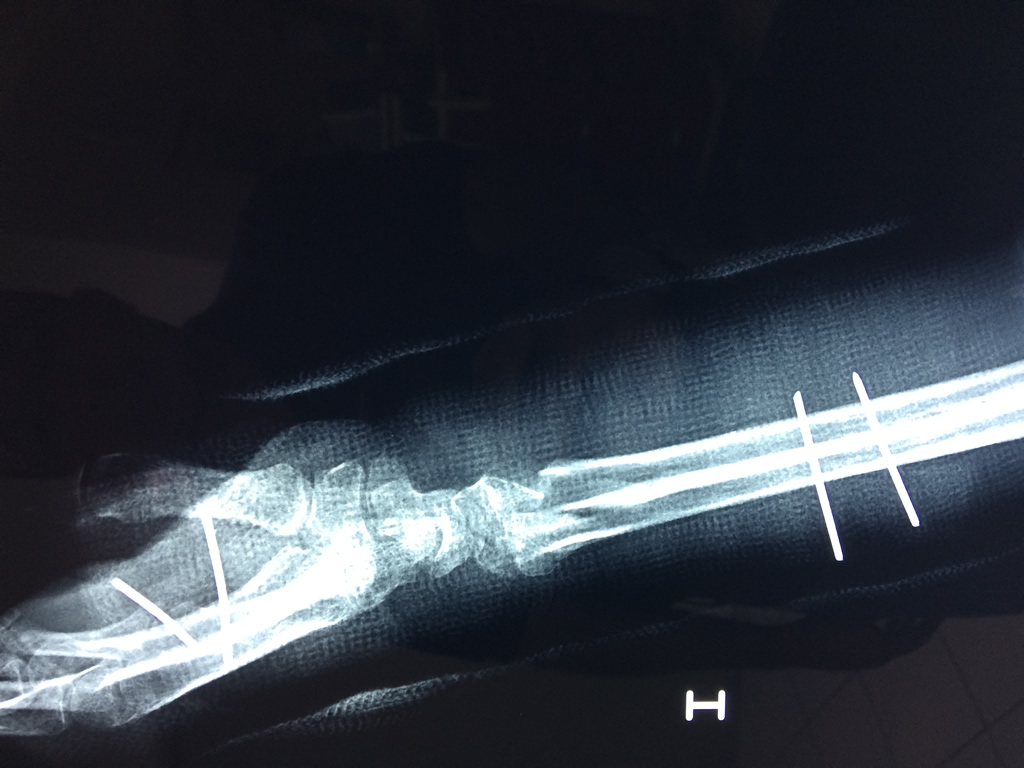

Cirugías de Peroné y Tibia

Los procedimientos más comunes en cirugía de la mano son aquellos destinados a reparar traumatismos, incluyendo lesiones de tendones, nervios, vasos sanguíneos, y articulaciones; huesos fracturados; y quemaduras, cortes, y otros daños de la piel.